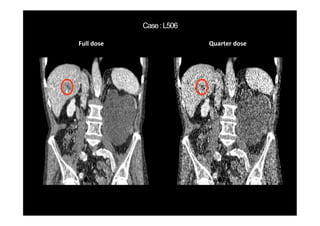

Routine dose Quarter dose

(Kang, et al, Medical Physics 44(10) 2017)

Routine dose AAPM-Net results

WavResNet results

(Kang et al, TMI, 2018)

MBIR Our latest Result

C D WavResNet results

Full dose Quarter dose